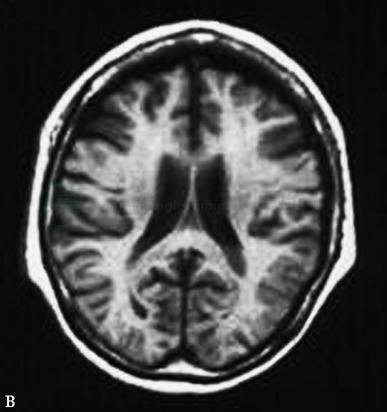

图11外伤后脑积水

轴位T2WI显示脑室系统扩展明显,蛛网膜下腔扩张